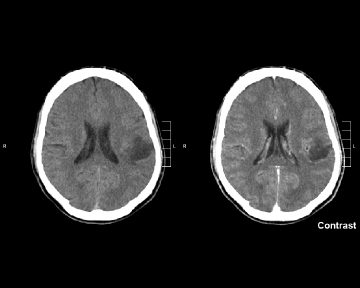

У «The New England Journal of Medicine» ( опубліковано результати подвійного сліпого дослідження 3-ї фази препарату ворасиденібу  у пацієнтів з гліомою (Mellinghoff IK, et al., 2023). Препарат від компанії «Servier» ще не отримав регуляторного схвалення у США та ЄС, і знаходиться на розгляді із статусом швидкого проходження (fast track) - у першому, та орфанного препарату (orphan medicine) – у другому випадку. Якщо регулятори приймуть позитивне рішення, ворасиденіб може стати першою таргетною терапією гліоми низького ступеня злоякісності.